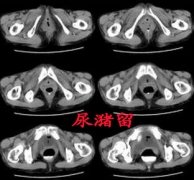

6旬老人肚子时大时小 原来是得了尿潴留

孙悟空会72变,身体可大可小,可高可瘦。当然,这终究是故事里的人物,是当不了真的。然而,近期不少新闻媒体都报道一则新闻,新闻中的老人他也会变戏法,他的戏法就是肚...

2015-04-09查看详情